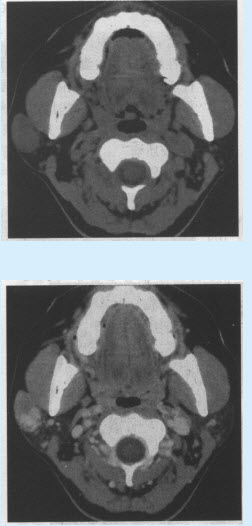

患者,女,30岁。无意中发现右侧面部包块半年余。CT检查如下图,诊断为()

A:腮腺混合瘤

B:腮腺淋巴瘤

C:腮腺神经鞘瘤

D:腮腺畸胎瘤

E:腮腺囊肿